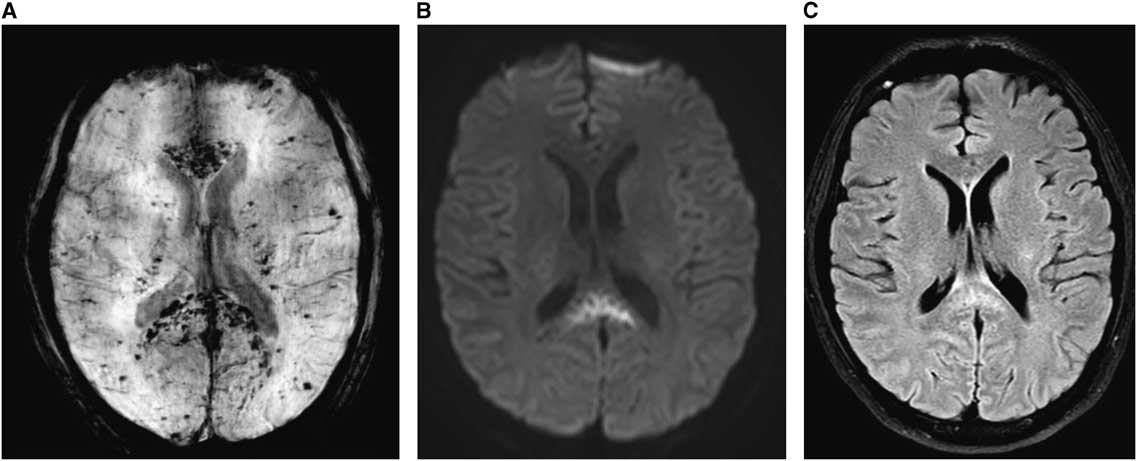

A 33-year-old man with no known medical history presented to the hospital with bruising and a diffuse petechial rash. He was found to have aplastic anemia, with hospital course complicated by septic shock requiring intubation, pressors, management with broad-spectrum antibiotics and antifungals, and multiple packed red blood cell and platelet transfusions. Following extubation, he was briefly delirious, for which magnetic resonance imaging (MRI) was obtained, showing scattered areas of susceptibility artifact, compatible with microhemorrhages in the subcortical deep white matter and cerebellum, with an unusual predominance in the corpus callosum. Restricted diffusion was seen in the genu and splenium of the corpus callosum (Figure 1). The patient gradually recovered and was discharged home.

Figure 1 (A) Susceptibility-weighted images (SWI): innumerable scattered areas of susceptibility artifacts, compatible with microhemorrhages predominantly in the corpus callosum. (B) Diffusion-weighted images (DWI): splenium of the corpus callosum demonstrates restricted diffusion. (C) T2 FLAIR: hyperintensity in splenium correlating to the region of restricted diffusion.

Microhemorrhages affecting the deeper structures of the brain are not unusual in the setting of shock and thrombocytopenia due to dysregulation of cerebral blood flow and blood–brain barrier breakdown.Reference Sharshar, Annane, de la Grandmaison, Brouland, Hopkinson and Françoise 1 However, microhemorrhaging predominantly affecting the corpus callosum is a rare finding, sometimes associated with high-altitude cerebral edema (HACE).Reference Fitsiori, Nguyen, Karentzos, Delavelle and Vargas 2 Radiographic and neuropathological studies in HACE show lesions in the splenium and the genu of the corpus callosum, though not to the degree seen in our patient.Reference Kallenberg, Dehnert and Dörfler 3 Similar findings have also been reported in extracorporeal mechanical oxygenation (ECMO),Reference Shah and Armstrong 4 though in our patient it likely stemmed from severe disease burden, inflammation, and platelet dysfunction.